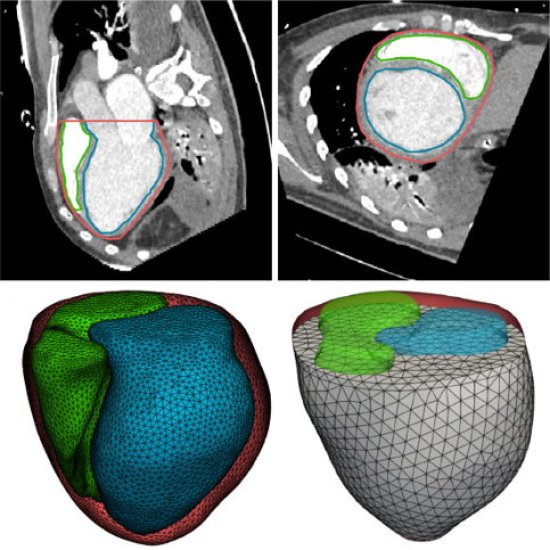

Medizinische Notfälle erfordern präzise Kommunikation, auch unter extremen Bedingungen. Forscher testeten daher auf einer simulierten Mondoberfläche Anleitungen zur medizinischen Versorgung bei einer Herzrhythmusstörung. Künstliche Intelligenz unterstützt zudem die Radiologie: An der Universitätsmedizin Göttingen markiert ein neues KI-Assistenzsystem Frakturen in Röntgenbildern innerhalb von Sekunden. In wenigen Tagen startet die MEDICA 2025; auf der Messe in Düsseldorf präsentieren hunderte Start-ups innovative Medizintechnik-Lösungen. Viel Spaß beim Lesen!

News • Patientenspezifisches Modell

Personalisierte Medizin fürs Herz: Mit KI-gestützten digitalen Zwillingen wollen Forschende kardiovaskuläre Erkrankungen besser verstehen und individuelle Behandlungen optimieren. |